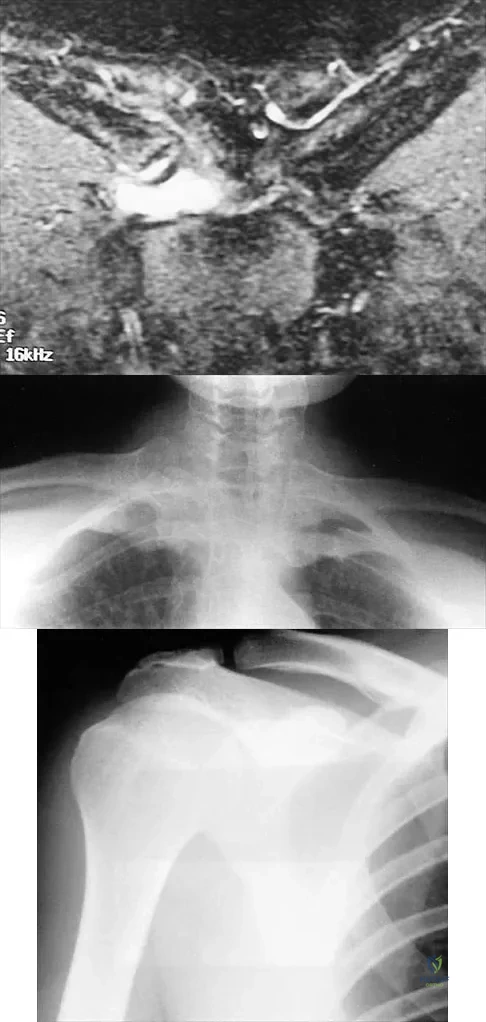

A 43-year-old former professional hockey player reports severe pain in his chest after being checked from the side in a pick-up hockey game. An MRI scan and plain radiographs are shown in Figures 25a through 25c. What is the most likely diagnosis?

Explanation